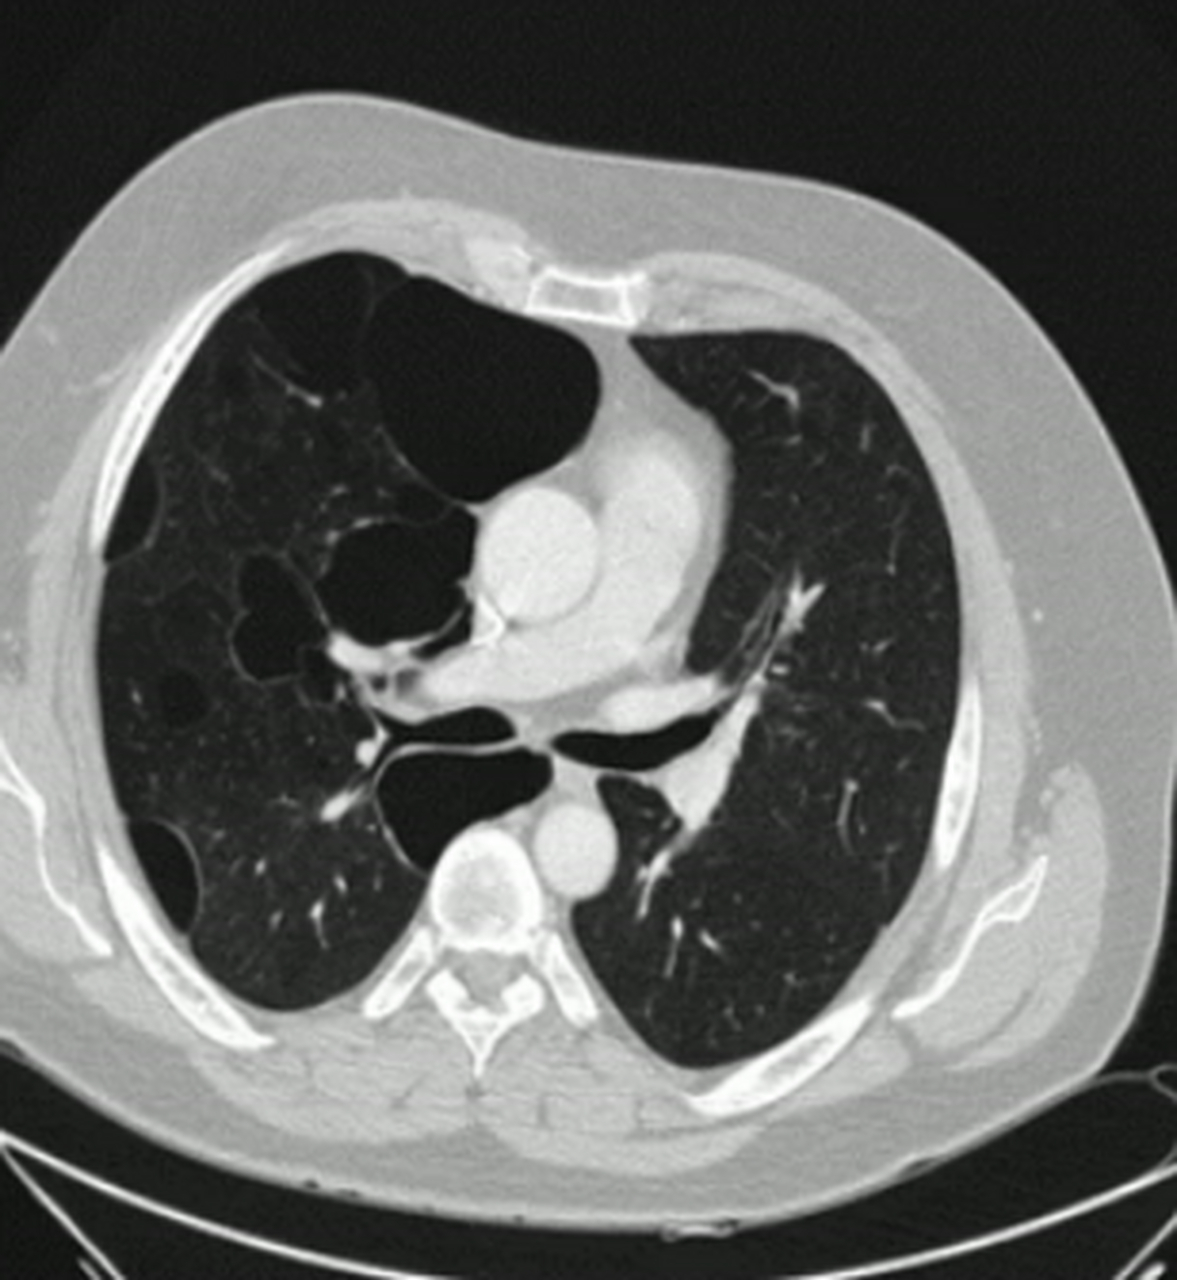

ct经典图谱31:肺大泡?淋巴细胞性间质性肺炎?